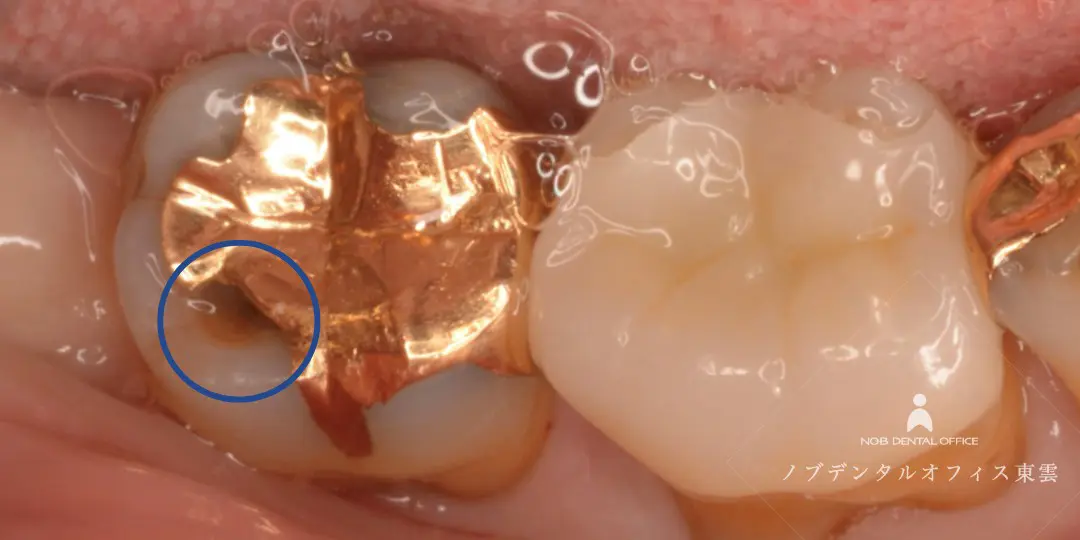

「奥歯に物が詰まる」とご来院。虫歯の再治療を行いました。

診察の結果、写真内・赤丸の歯はセラミック治療した歯なのですが、詰め物の奥に二次う蝕(虫歯)が認められました。

う蝕検知液で虫歯の部分だけを染め出し、健康な歯をできるだけ削らないよう注意して治療します。

虫歯の患部を丁寧に削った後は、CRで歯を保護し、ジルコニアインレーをセットします。

う蝕検知液で虫歯の部分だけを赤く染めた様子。

虫歯を取り除いた後、CRで歯を保護した様子